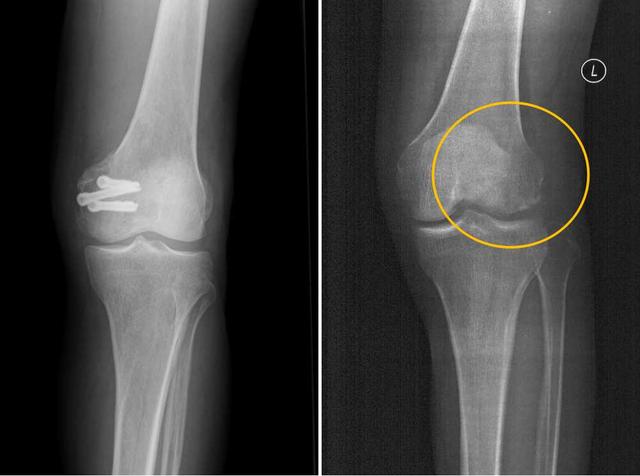

今年5月份 , 患者张强(化名) , 不慎扭伤 , 造成左股骨远端骨折 。 入驻医院后 , 医院骨科雷伟教授团队针对患者骨折部位靠近关节面 , 使用金属螺钉固定时应力过大 , 会影响骨折愈合 , 一年后还需要实施惯例手术再次取出 , 形成二次创伤的实际 。 经过反复论证细致阅片后决定 , 对其手术时使用本院骨科自主研发的可降解蚕丝螺钉固定 。 术后患者CT片中没有任何伪影 , 可以清晰地看到骨折块已经完全复位 , 解除了患者二次手术取出的负担和困扰 。

术前(左)及术后(右)三维CT图像 受访者供图